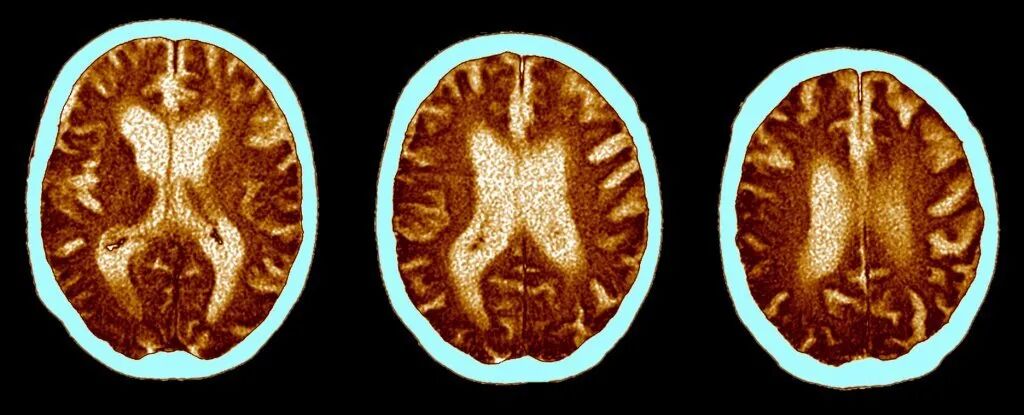

这项发表在《电子临床医学》(eClinicalMedicine)杂志,由剑桥大学和伦敦帝国理工学院联合研究的报告显示,越来越多的证据表明,那些严重感染新冠的患者更可能出现持久认知问题。

这些认知问题与50至70岁之间因衰老造成的影响相似,相当于失去10个智商点(IQ points)。

科学家们对2020年3月至7月期间,因感染新冠导致重症且平均接受了6个月住院护理的46人,使用Cognitron平台进行详细的计算机化认知测试。结果发现,与对照组相比,这些严重新冠感染者的准确度较低,反应时间较慢。

通过将结果与66,008名普通公众进行比较,研究人员估计,认知障碍程度平均与50至70岁之间持续20年的衰老状况相似,相当于失去10个智商点。

该研究的资深作者、剑桥大学的David Menon教授说,认知障碍常见于各种神经系统疾病,包括痴呆症,甚至常规老化,但新冠导致的认知障碍与这些都不同。

大脑扫描图像 | 图片来源ScienceAlert

参与研究者在言语类比、推理等任务上的得分特别低,为早期普遍报道重症新冠感染者找词困难的问题提供了支持。同时也与之前在感染新冠后观察到的大脑前额叶网络内的大脑葡萄糖消耗减少相一致,该网络负责注意力、复杂问题的解决和工作记忆等功能。